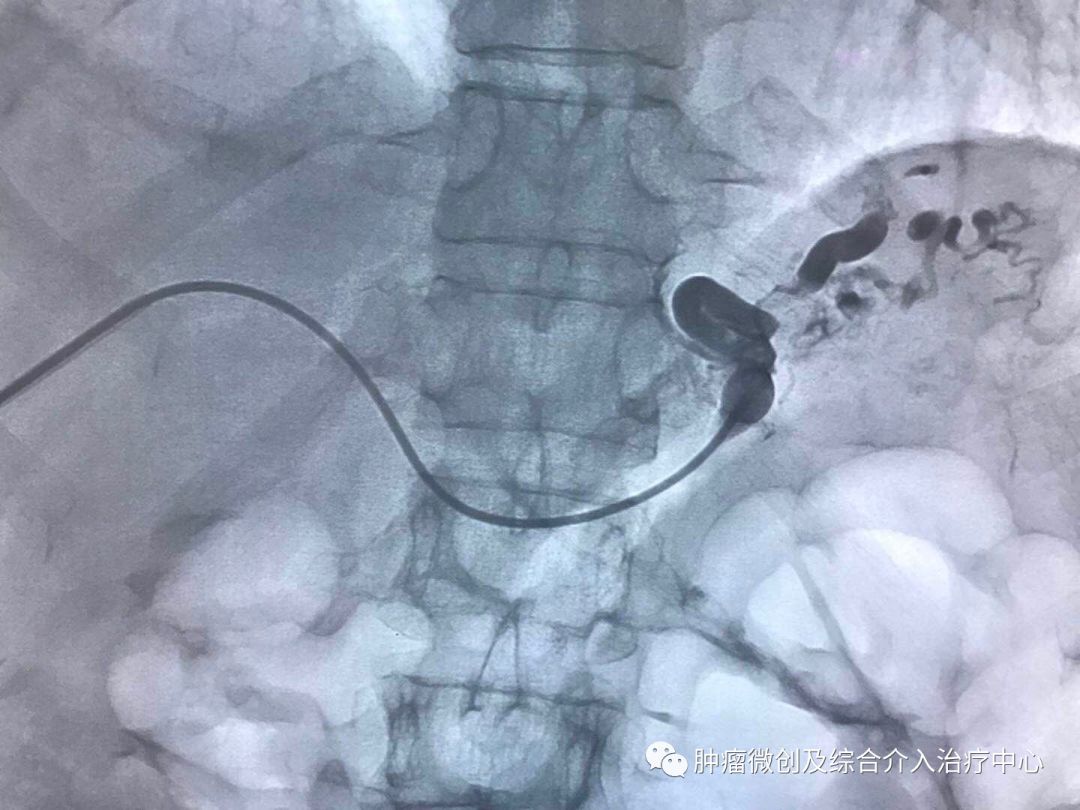

(肝静脉-门静脉穿刺成功,门脉高压,门静脉扩张明显)

(肝静脉-门静脉支架置入搭桥术,分流门脉部分血流,门脉压力降低)